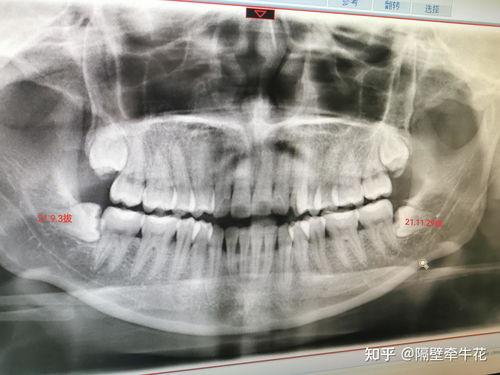

在拔牙前,医生会先给你进行口腔检查,确认智齿的位置和生长情况。医生会给你进行局部麻醉,让你在拔牙过程中不会感到疼痛。